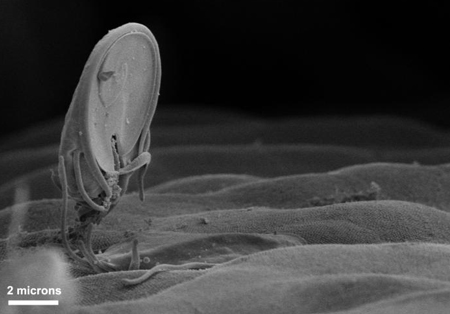

Scanning electron micrograph of Giardia trophozoite on the mucosal surface of the intestine. The ventral adhesive disc, which facilitates adherence to the intestinal surface, can be seen on the underside of the organism

Courtesy of Dr Stan Erlandsen; CDC Public Health Image Library (PHIL)